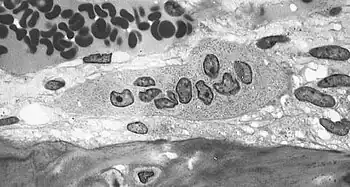

Osteoblasts actively synthesizing osteoid containing two osteocytes.

Osteoclast, with bone below it, showing typical distinguishing characteristics: a large cell with multiple nuclei and a "foamy" cytosol.